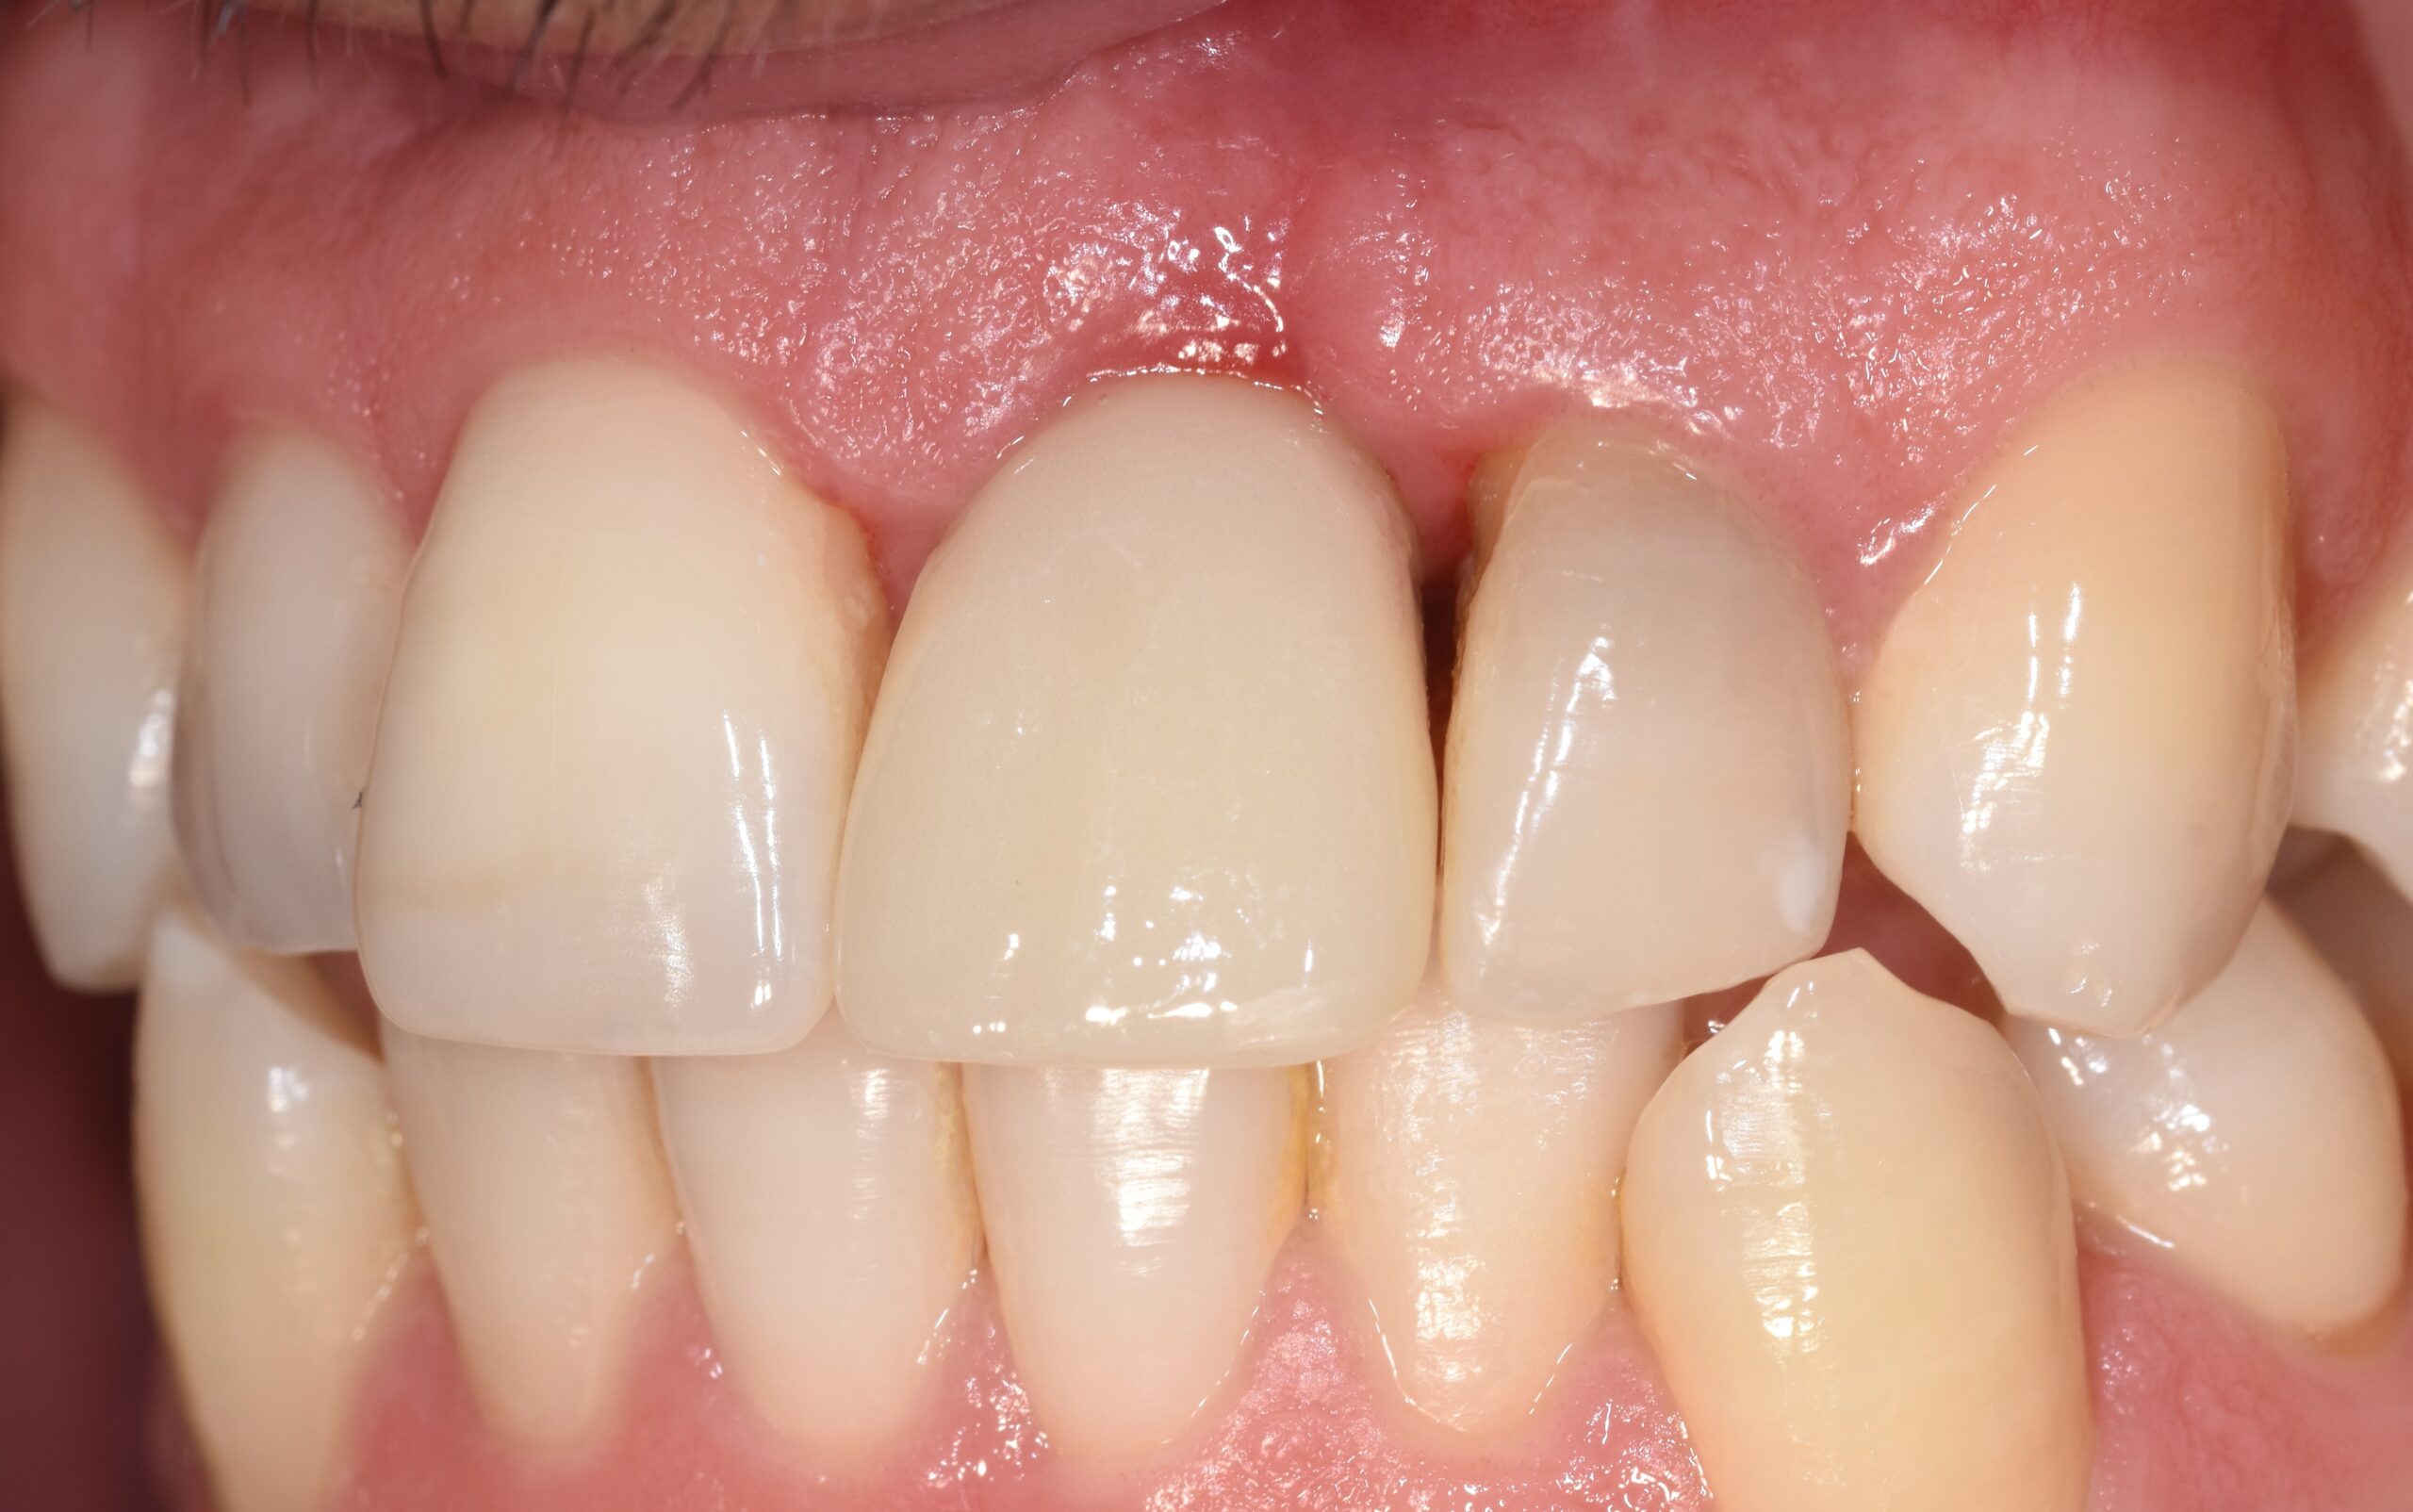

Previa impronta ottica, veniva preparato un Maryland provvisorio di adeguata forma (Figura 4) applicato sul gruppo frontale dopo estrazione atraumatica dell’elemento (Figura 5).

Il provvisorio, di forma ovoidale della parte intra-alveolare, sigillava senza compressione l’alveolo, penetrando in esso per circa 3 mm (Figura 6) (14). Prima della sua applicazione, l’alveolo veniva liberato dal tessuto granulomatoso e riempito con spugna di collagene. Nessun innesto veniva applicato nell’alveolo (15).

Il sito veniva nuovamente sigillato con il ripristino del Maryland. Il basso valore di torque implantare sconsigliava l’inserimento di un provvisorio immediato (16).